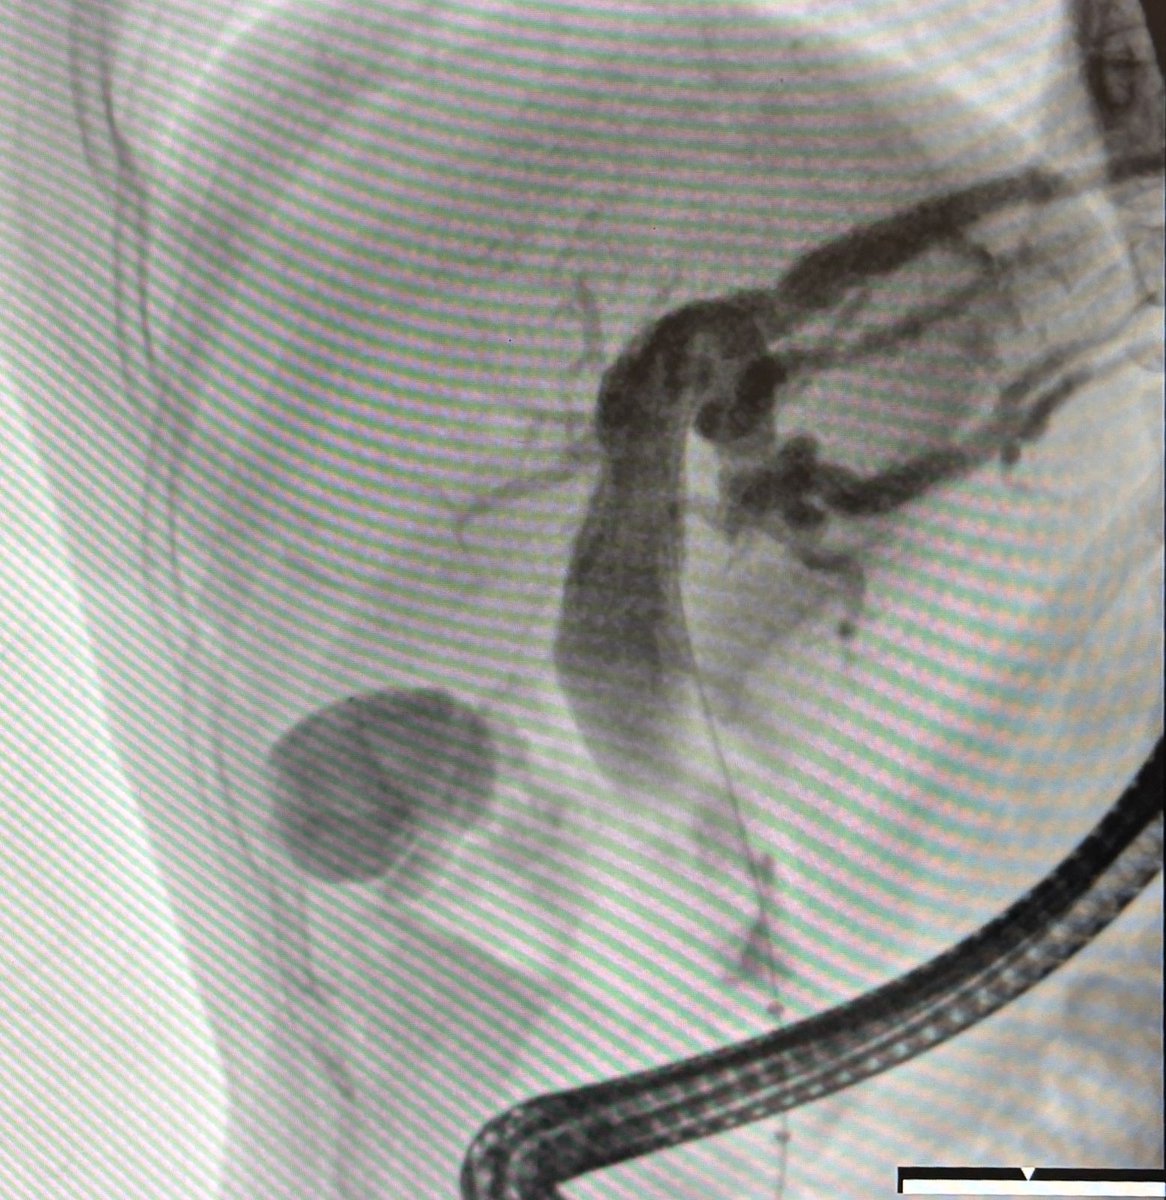

M/F referred for Obstructive Jaundice due to choledocholithiasis now here for ERCP! Cholangiogram suggested low-lying cystic duct with impacted stone, likely Mirizzi Syndrome. What are your thoughts about further management?